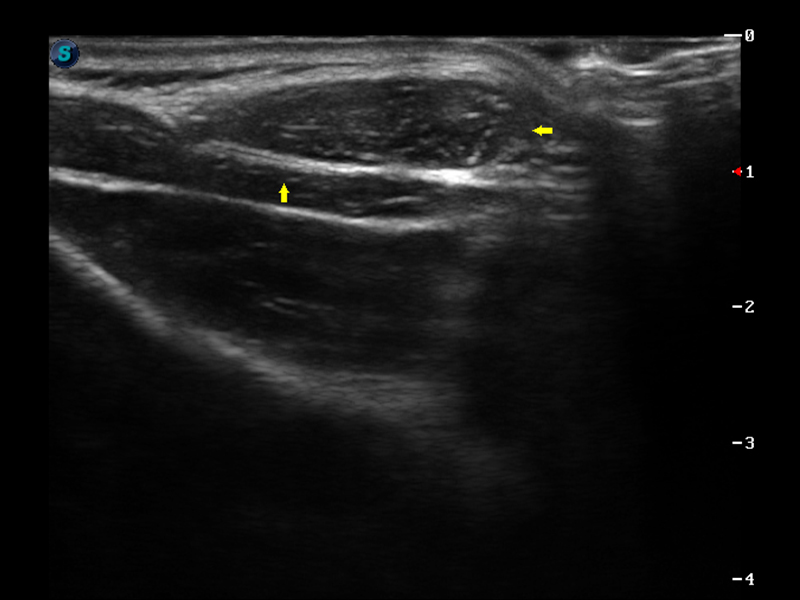

S9便携式彩色多普勒超声诊断仪是玖鼎集团研发的高端便携彩超设备,外观设计新颖、产品性能卓越。S9在便携超声领域采用了突破传统的触摸屏交互设计,并以先进的软件硬件技术和设计理念,为您带来清晰的图像质量、稳定的工作性能和便捷的操作体验。

μ-Scan微米成像